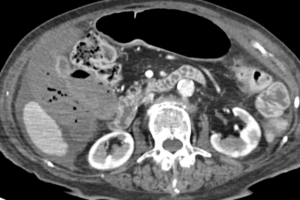

Caso 03

DIAGNÓSTICO DIFERENCIAL: